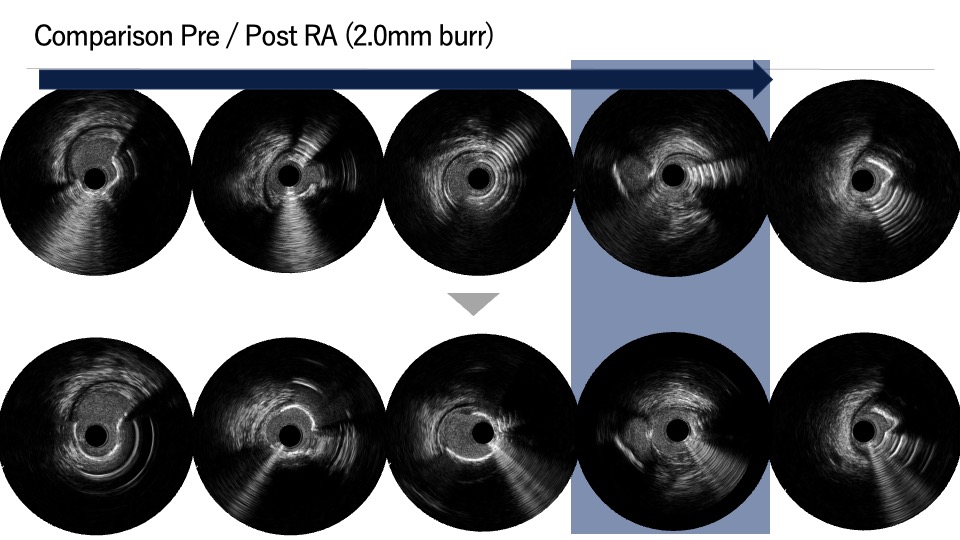

PCI was first performed for the LCx, using orbital atherectomy followed by cutting balloon predilatation and drug-coated balloon therapy with good angiographic result. One month later, PCI was attempted for the LAD lesion using a 8F system via right femoral approach. Intravascular ultrasound (IVUS) revealed a diffusely eccentric calcified plaque located on the septal side. While wire bias in the proximal segment was toward the calcified plaque, the distal segment showed tenting of the wire toward a plaque-free site on the diagonal branch side. At this point, we considered that debulking of the distal segment would be a high risk of vessel injury. We hypothesized that performing proximal segment debulking that had a favorable wire bias might shift the overall wire bias toward the septal side. Then Only proximal OAS was performed using pull-back ablation.Follow-up IVUS showed disappearance of distal tenting and favorable wire bias toward the calcified plaque. As a result, OAS was safely performed in the distal segment as well. Additional debulking of the residual calcified plaque was conducted with a 2.0 mm Rotablator. IVUS confirmed effective debulking without vessel injury in the area of concern. The entire lesion was then dilated with a CB; however, a dissection with hematoma occurred, and a drug-eluting stent (DES) was implanted. Final IVUS demonstrated acceptable stent expansion, and final angiography showed no residual stenosis or flow limitation.